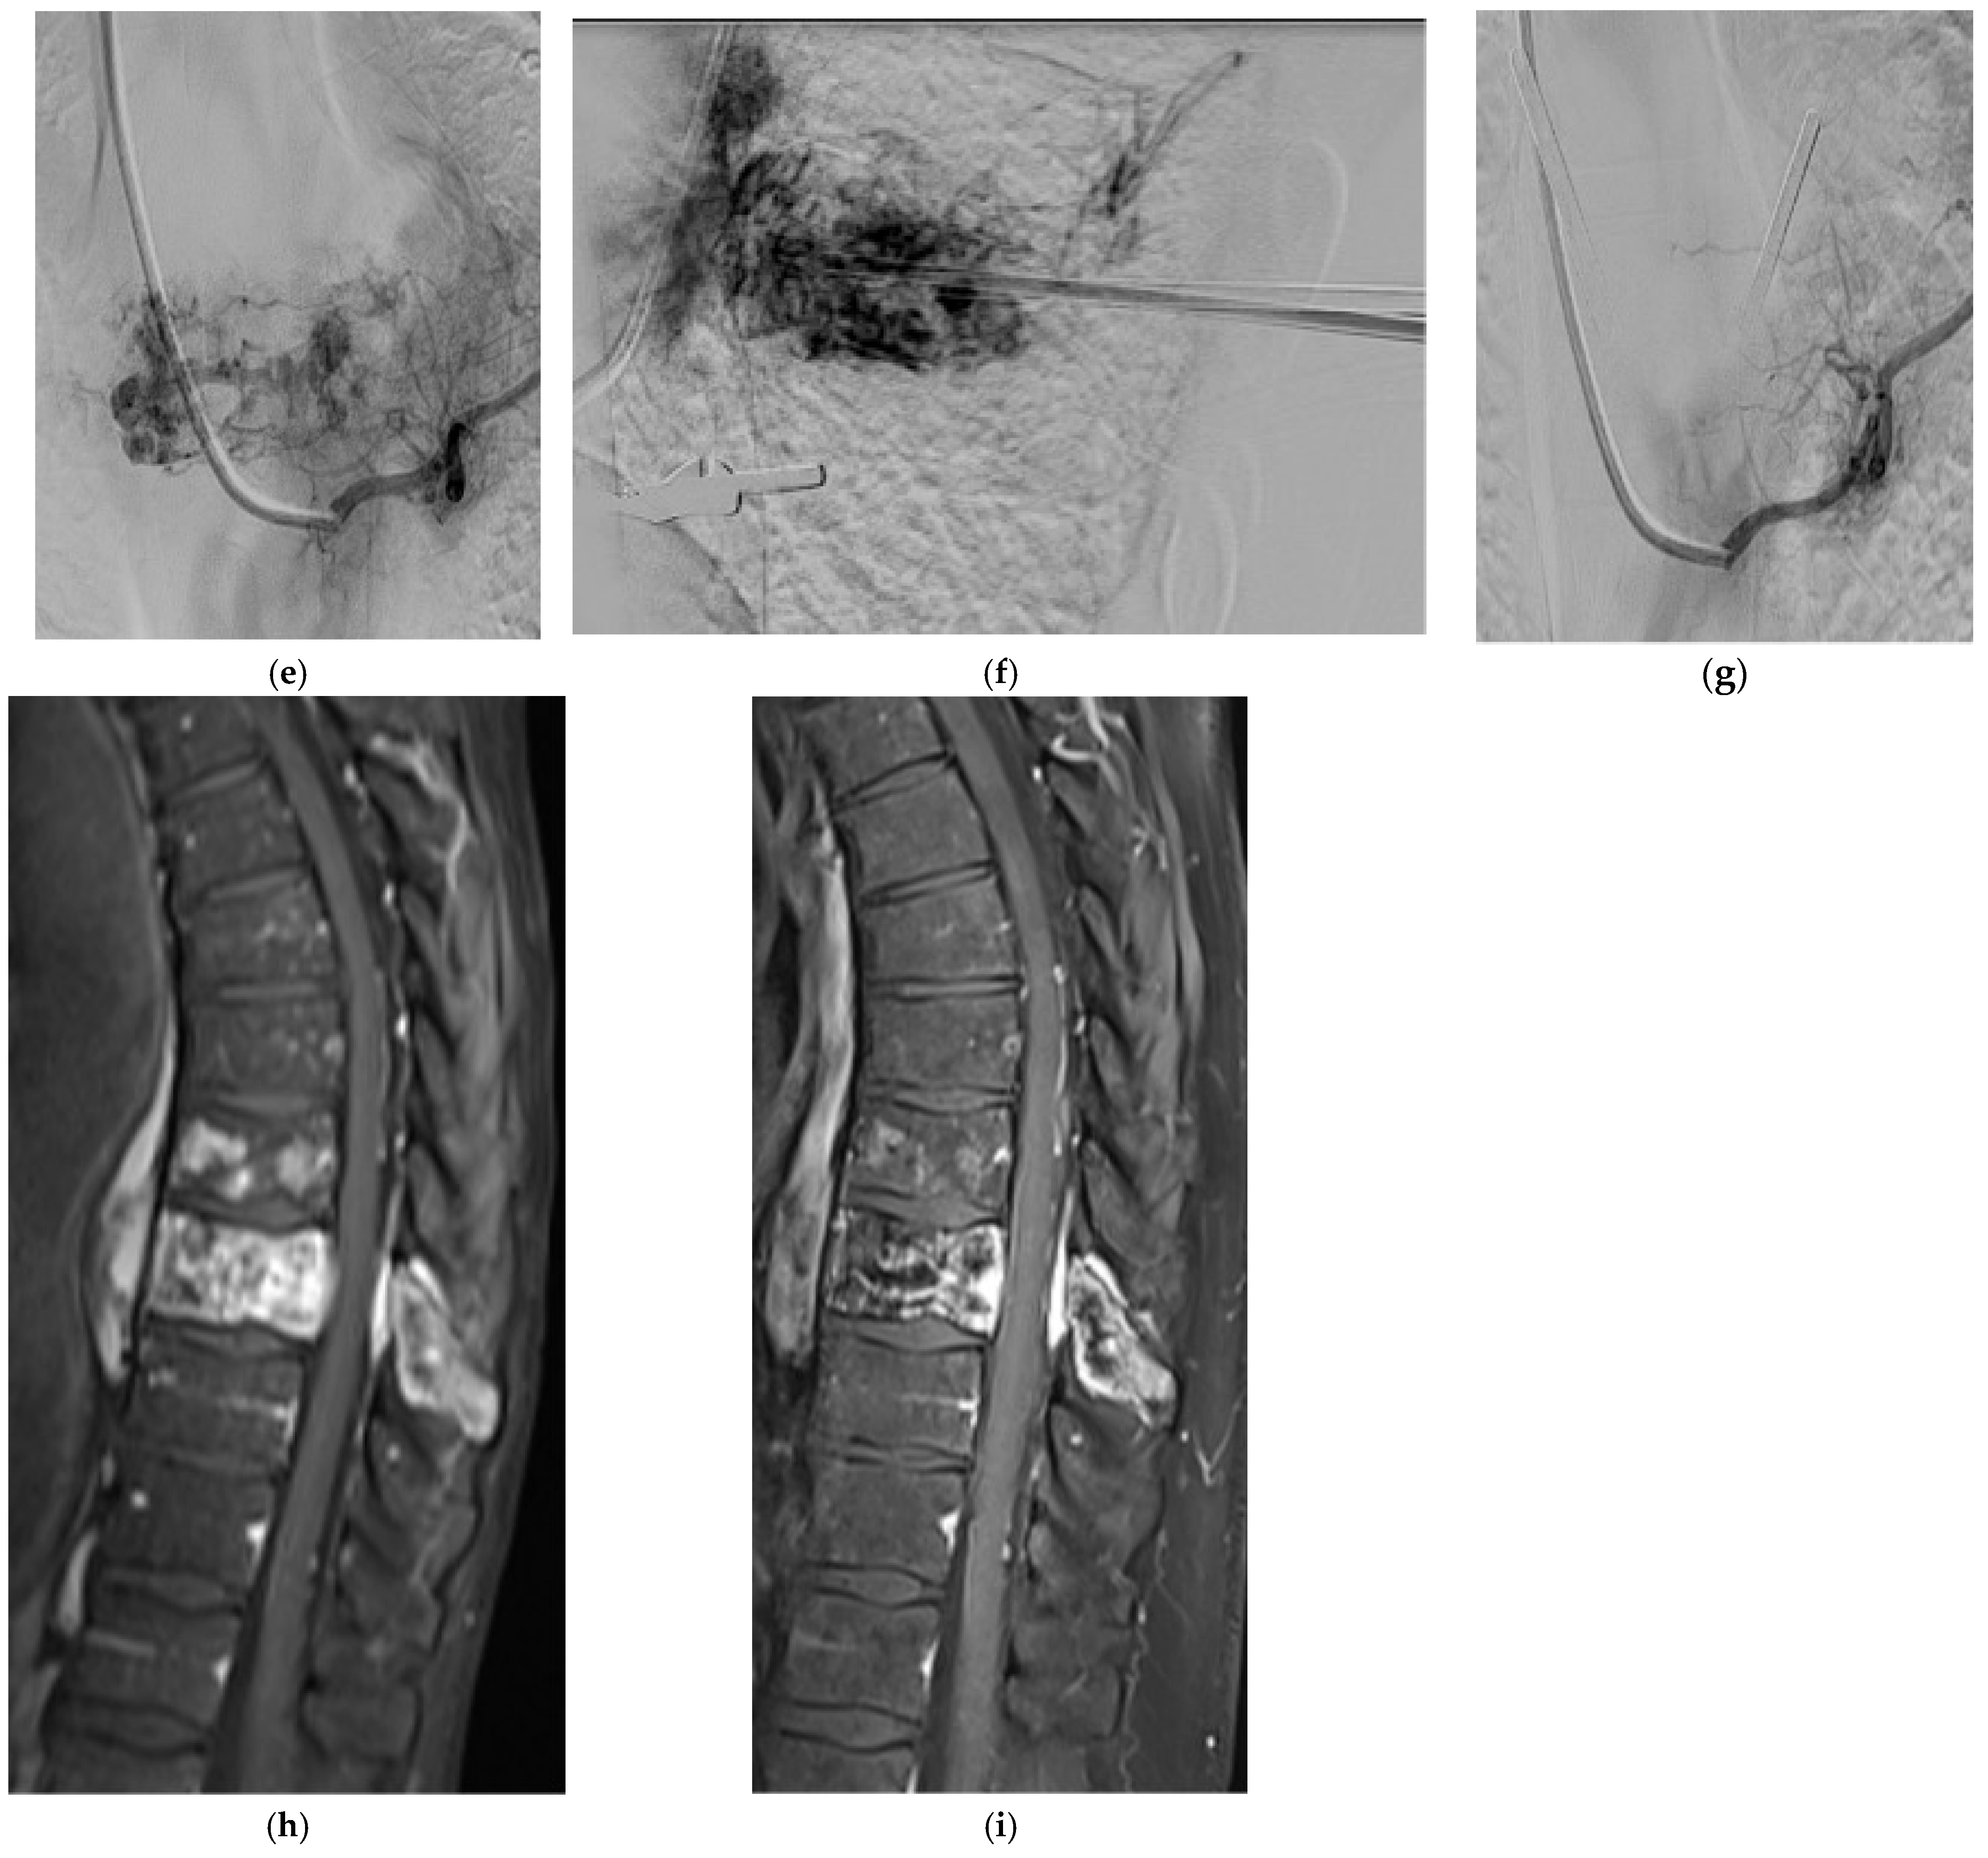

2.5.1. Hemangioma

2.5.2. Aneurysmal Bone Cyst